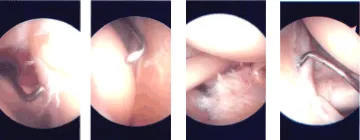

Intraoperative Arthroscopy Images

Labral tear could be seen along the superior aspect without involvement of the biceps anchor. Debridement of the labrum was done with the use of a shaver. Articular site high-grade partial thickness tears could be seen in the supraspinatus.

Debridement was done and tagging was done with the use of PDS suture. Rest of examination of the glenohumeral joint was intact. Pictures were taken and saved. The arthroscope was inserted into the subacromial region. Shaver was introduced from anterosuperior portal. Debridement of the bursa of the subacromial space was performed with the use of a shaver.

The rotator cuff was examined in the region of the PDS and found to have near complete tearing of the supraspinatus. A shaver was used to complete the tear. Debridement of the tear and the head of the humerus was performed in preparation for the repair.

A plan from distal clavicle excision was performed, was made and 6.0 bur was used to excise the articular surface of the AC joint. About a centimeter of the distal clavicle was excised to the posterior as well as anterior superior portal. Final pictures were taken and saved.

Intraoperative Arthroscopy Images.